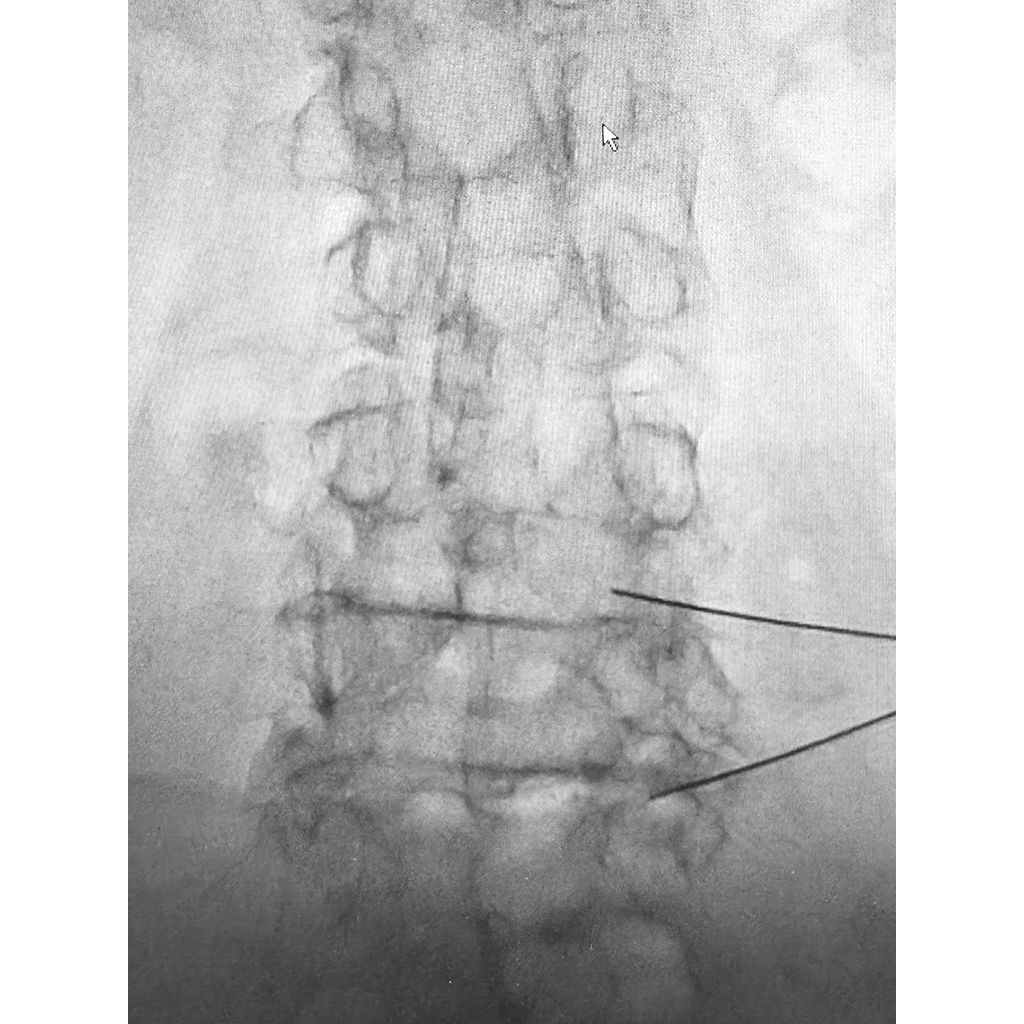

MRI

腰のMRI検査です。1年前に椎間板治療は行っていますが、脊柱管狭窄症部分の炎症または神経周囲の癒着障害や神経障害の後遺症などにより、しびれが残存している可能性が示唆されます。